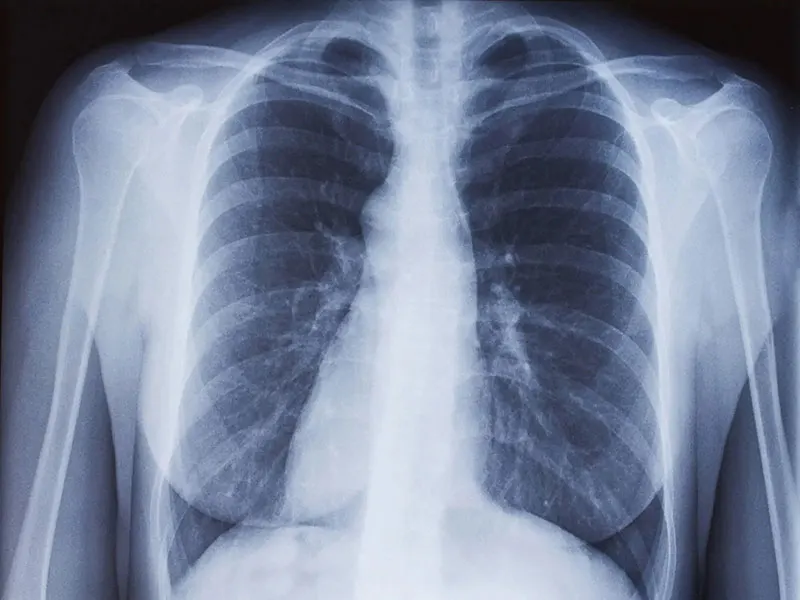

• निमोनिया एक फेफड़ों का संक्रमण है जो वायरल, बैक्टीरियल या फंगल संक्रमण के कारण होता है।